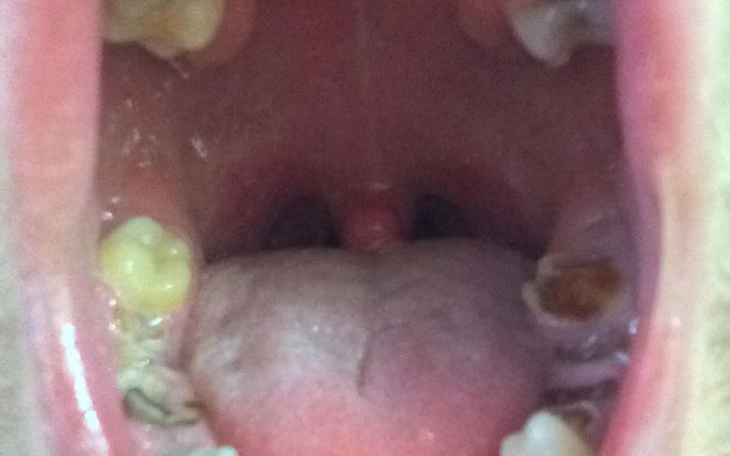

Witam wszystkich, mam na imie Sebastian, lat 27, jestem kawalerem. Od lat mam pewien problem a mianowicie mam problem z moimi zebami, od 3 lat nie potrafie sie juz szczerze usmiechac.. zycie przestalo mi sie podobac. Aktualnie jestem w takim stanie ze wiekszosc z moich zebow ma ubytki a niektorych wcale nie ma, jedynym wyjsciem jest usuniecie pozostalych zebow i wstawienie implantow, jest to bardzo kosztowne dlatego tez potrzebuje pieniedzy na leczenie. Mam stala prace, nie zarabiam zbyt wiele, mieszkam sam i musze tez wszystko utrzymac, staram sie cos po troche odkladac na ten cel ale nie jest latwo. W ostatnim czasie moj stan sie pogorszyl poniewaz ukruszyly mi sie nawet jedynki, ciezko a zarazem wstyd jest mi z kims rozmawiec prosto w oczy... staram sie unikac kontaktu z ludzmi z tego powodu. Musze cos z tym zrobic aby odzyskac swoje zycie i wkoncu zaczac czerpac z niego radosc, zawsze radzilem sobie ze wszystkim sam ale teraz musze prosic o pomoc, wiec jesli tylko masz taka mozliwosc to bede ci bardzo wdzieczny, mozesz pomoc zmienic moje zycie. Z gory dziekuje wszystkim ktory maja dobre serca. pozdrawiam